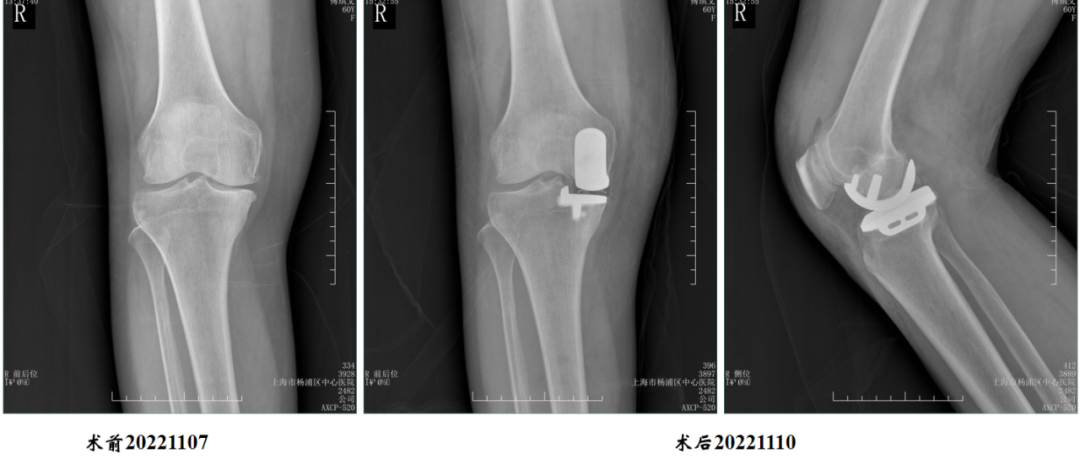

病例1:胫骨假体后倾角度>7°

问题:胫骨假体后倾角度12°,轻度膝外翻

病例1:胫骨假体翻修

UKA to UKA 更换胫骨假体